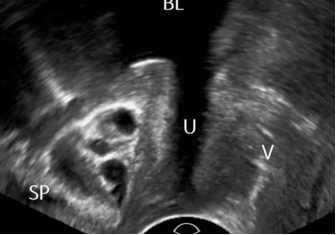

▶ 1、经直肠或经阴道途径:可应用双平面腔内探头或者腔内端射式探头进行检查,应用双平面腔内高频探头扫查时可获得尿道正中矢状切面及横切面。

▶ 1、静息状态:可观察尿道形态、走行、回声是否正常、前后壁是否连续等,并进行相应测量;可对尿道占位性病变进行评估。

▶ 2、排尿状态:主要观察尿道通畅性、腔面连续性、光滑度、尿液流出路径以及尿道腔内情况。一般应用于尿瘘、尿道狭窄、尿道憩室、尿道结石、尿道腔内病变等疾病的评估。